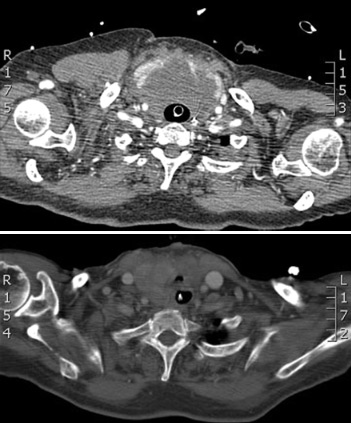

CT of neck pre- and post-operative: tracheal compression by a thyroid lymphoma

Van la Parra RFD, Kroeze J, van Die J, et al. Progressive respiratory distress due to neck mass. BMJ Case Reports. 2009; doi:10.1136/bcr.11.2008.1193